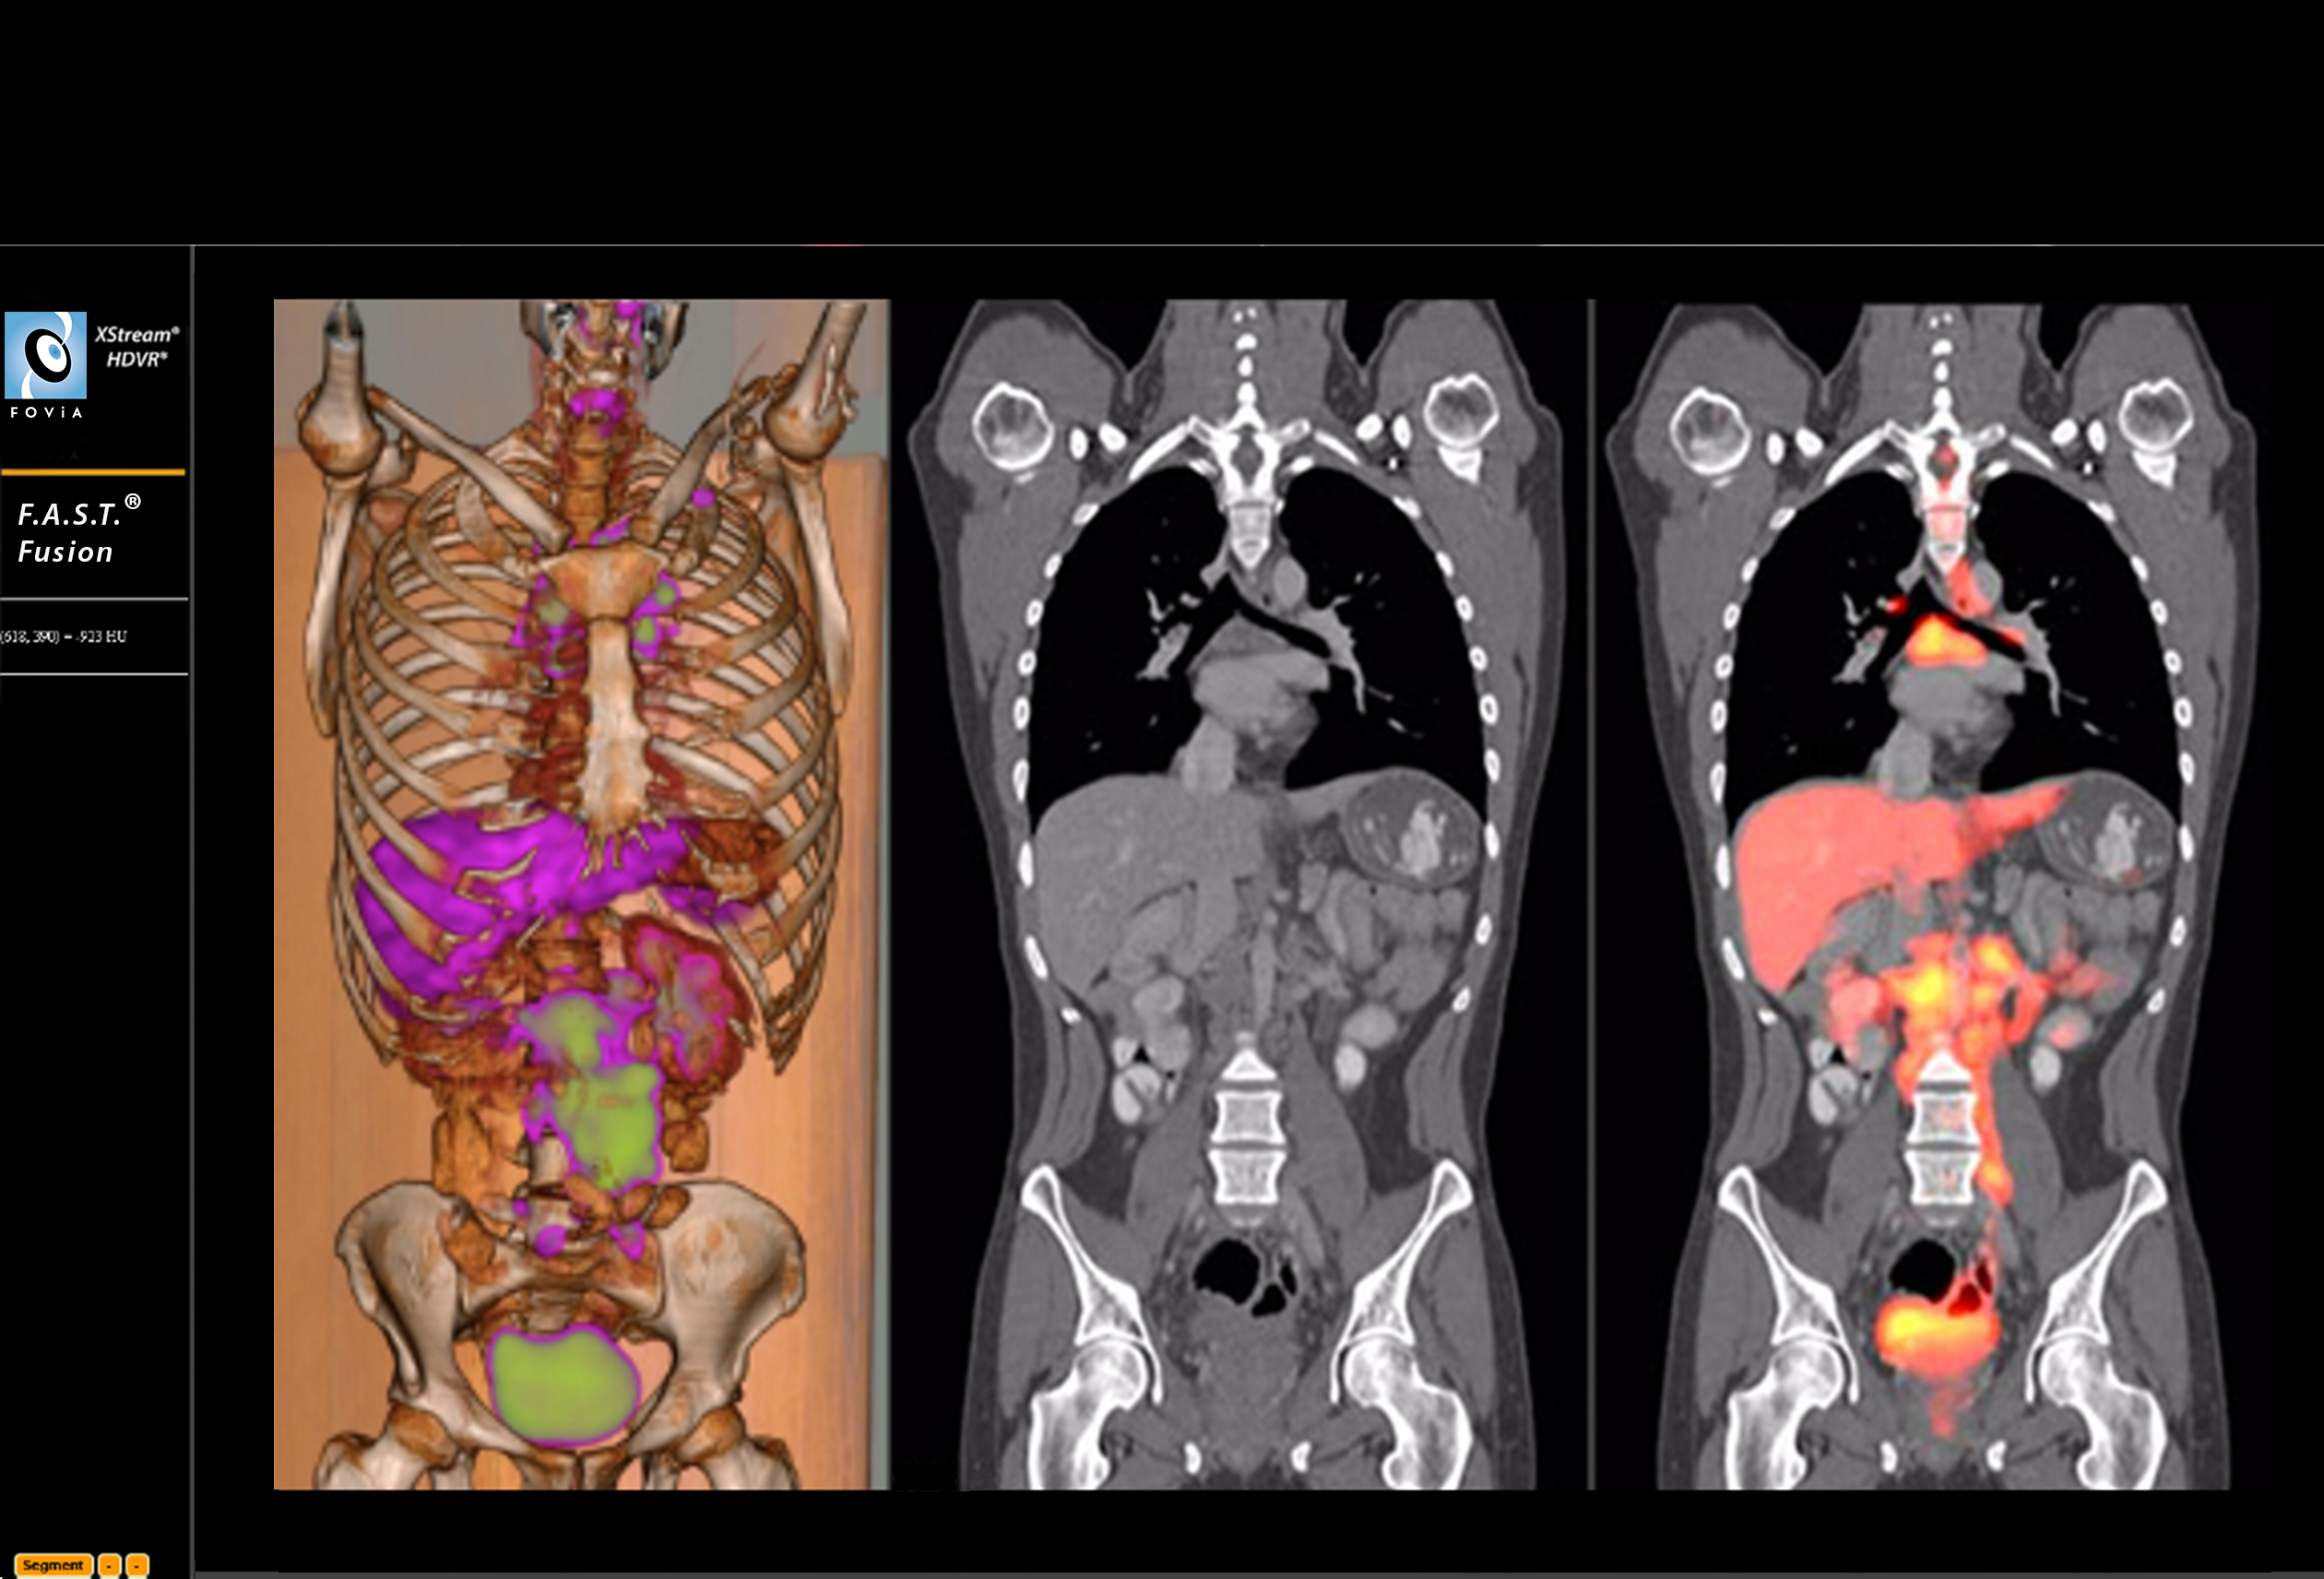

F.A.S.T. Fusion Workflow

F.A.S.T. Fusion Workflow